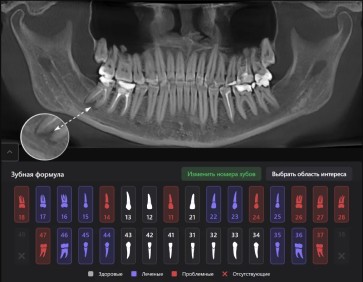

Диагнокат (DIAGNOCAT)

Это сверхточная диагностика полости рта, применяемая для исследования различных проблем в зубных специализациях: ортодонтия, терапевтическая стоматология, челюстно-лицевая хирургия и т. д. Суть технологии заключается в мониторинге рентгеновских снимков и выявлении скрытых процессов, оказывающих негативное влияние на здоровье и целостность тканей.

Преимущество инновации перед другими заключается в формировании скрупулезного отчета об имеющихся посттравматических поражениях, которые могут повлечь за собой серьезные последствия. DIAGNOCAT умеет:

- определять состояние зубов и выявлять патологии в каналах и костях;

- находить анатомические образования в челюстно-лицевом аппарате;

- фиксировать наличие кариеса, пародонтита и пародонтоза;

- выделять дефекты протезирования и пломбирования.

Благодаря качественному изображению, где каждая проблема обозначена цветом, пациент и врач наглядно видят результат исследования. Первый понимает важность и целесообразность лечения. Второй ставит точный диагноз, благодаря всеобъемлющему анализу и назначает адекватную терапию.